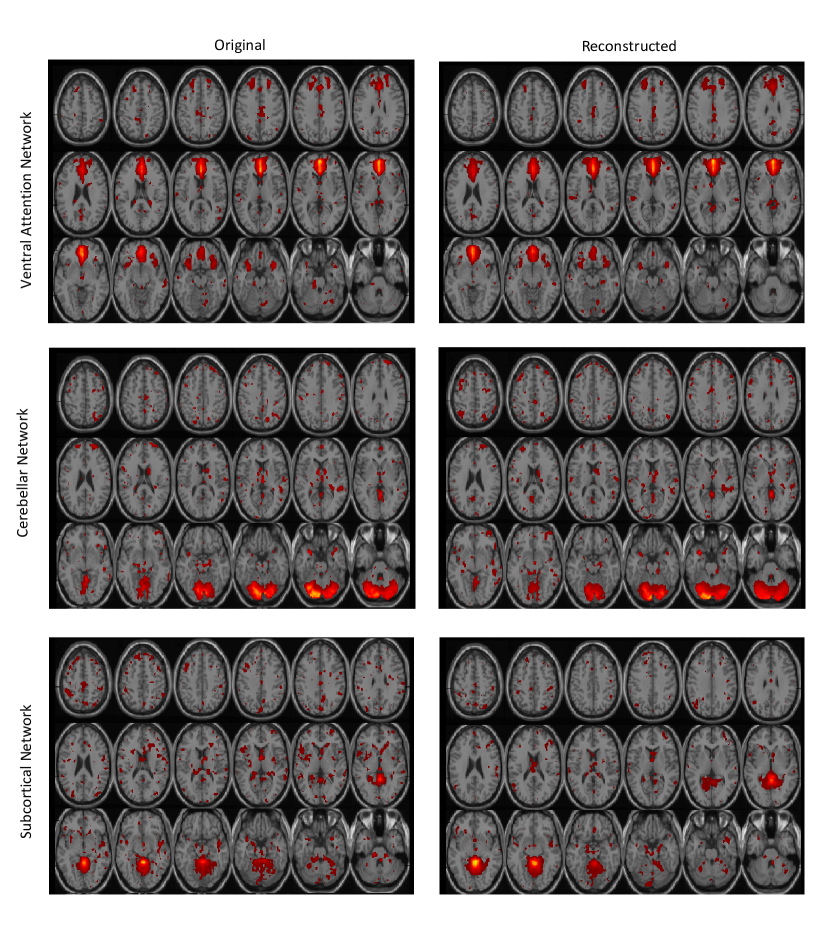

On the fMRI data reconstructed using the proposed DTSR method, we identified 56 ICs from the mean maps of reconstructed fMRI data of all 20 subjects. We manually arranged these ICs into various RSNs stated above. The spatial maps of some RSNs discovered by the fully available data and the DTSR reconstructed data are shown in Fig.6 to Fig.7. Left part of each figure represents networks identified using the fully available data and the right part represents networks identified using the DTSR reconstructed data. It is clear that spatial activation maps of RSNs obtained from the reconstructed data overlap significantly with the RSNs of the fully available fMRI data. From now onwards, ICs of DTSR reconstructed data will be mentioned as simply DTSR ICs (DTSR-ICs) and ICs of fully sampled original data will be mentioned as raw ICs (RICs). It is noticed that DTSR-IC maps are more enhanced compared to the RIC maps. This is perhaps due to denoising inherent within the CS reconstruction framework.

Refer to caption

Figure 6: Axial view of spatial maps of various RSNs where the left part of each figure represents networks identified using the fully available (original) data and the right part represents networks identified using the DTSR reconstructed data. Each row corresponds to results on one RSN. Number in brackets below each image represents independent component (IC) number obtained after group ICA.

Two observations are in order from the qualitative results (Fig.5-6): (i) intrinsic resting state networks are consistent and comparable to the fully sampled fMRI data. Hence, crude estimate of regularization parameters is sufficient for reconstruction; and (ii) the fidelity of the proposed method in maintaining temporal information is established via consistency of results and via observation of all RSNs.